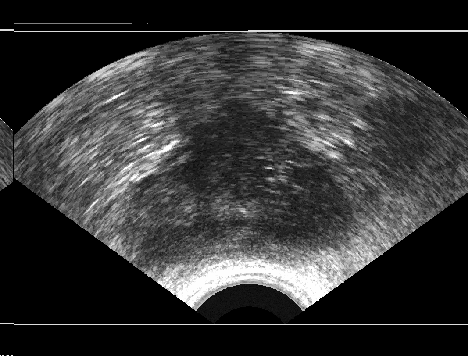

We generated 500 images from their corresponding gold-standard images. Furthermore, we generated 20 different segments for each image, assuming that there were 20 users. Figure 4 shows three examples of real and synthetic TRUS images. One should bear in mind that the purpose here was not to simulate the images realistically, but rather to have a base from which to generate variable segments from a perfect segment. Figure 5 shows an example of the gold segments and simulated user contours. The variability, coupled with the gold segment, is what is needed to validate our approach.

Sample images are depicted in Figure 6 (top row). Generally, one assumes that prostate segmentation is a relatively easy task. However, the variability of such segmentation remains considerable, and this is conspicuous in Figure 6 (bottom row).